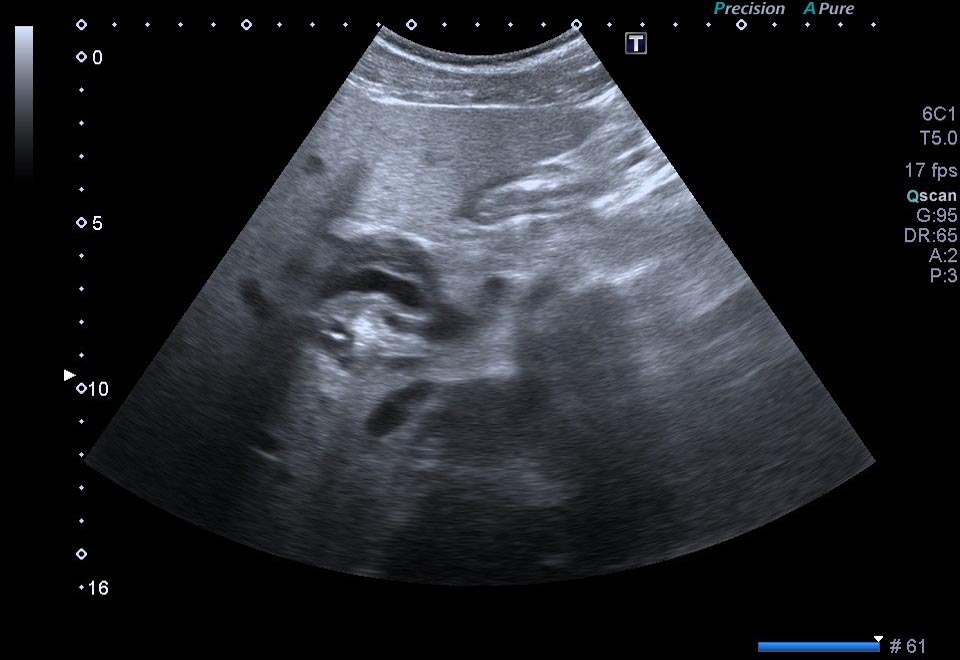

1. ¿Cuál de los siguientes hallazgos NO se encuentra en las imágenes ecográficas?

- A. Lesión hipoecoica que engloba la arteria hepática.

- B. Lesión hipoecoica que contacta con la cabeza pancreática.

- C. Dilatación del colédoco y del Wirsung.

- D. Permeabilidad de arteria hepática.

- E. Permeabilidad de la porta.